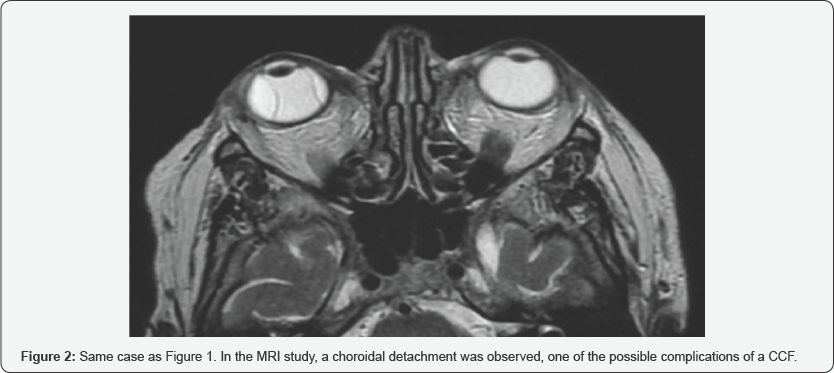

In a period of 1 year between March 2016 and May 2017, eight patients have been diagnosed and treated by CCF in our hospital. Of these eight patients, three were women and five men, with an average age of 52.9 years (range 25-77 years). All the patients in our series had exophthalmos, 62 % also associated diplopia and chemosis, and in 25 % they manifested headache or auscultate fro nto-orbital murmurs (Figure 1). In a patient with loss of visual acuity, a choroidal detachment was observed on MRI, a complication that can be associated with CCF (Figure 2). In 6 patients, the ocular symptoms were unilateral (75%): two patients with involvement of the right cavernous sinus and four patients with left involvement), being bilateral in the two remaining patients (Figure 3) [1-4].